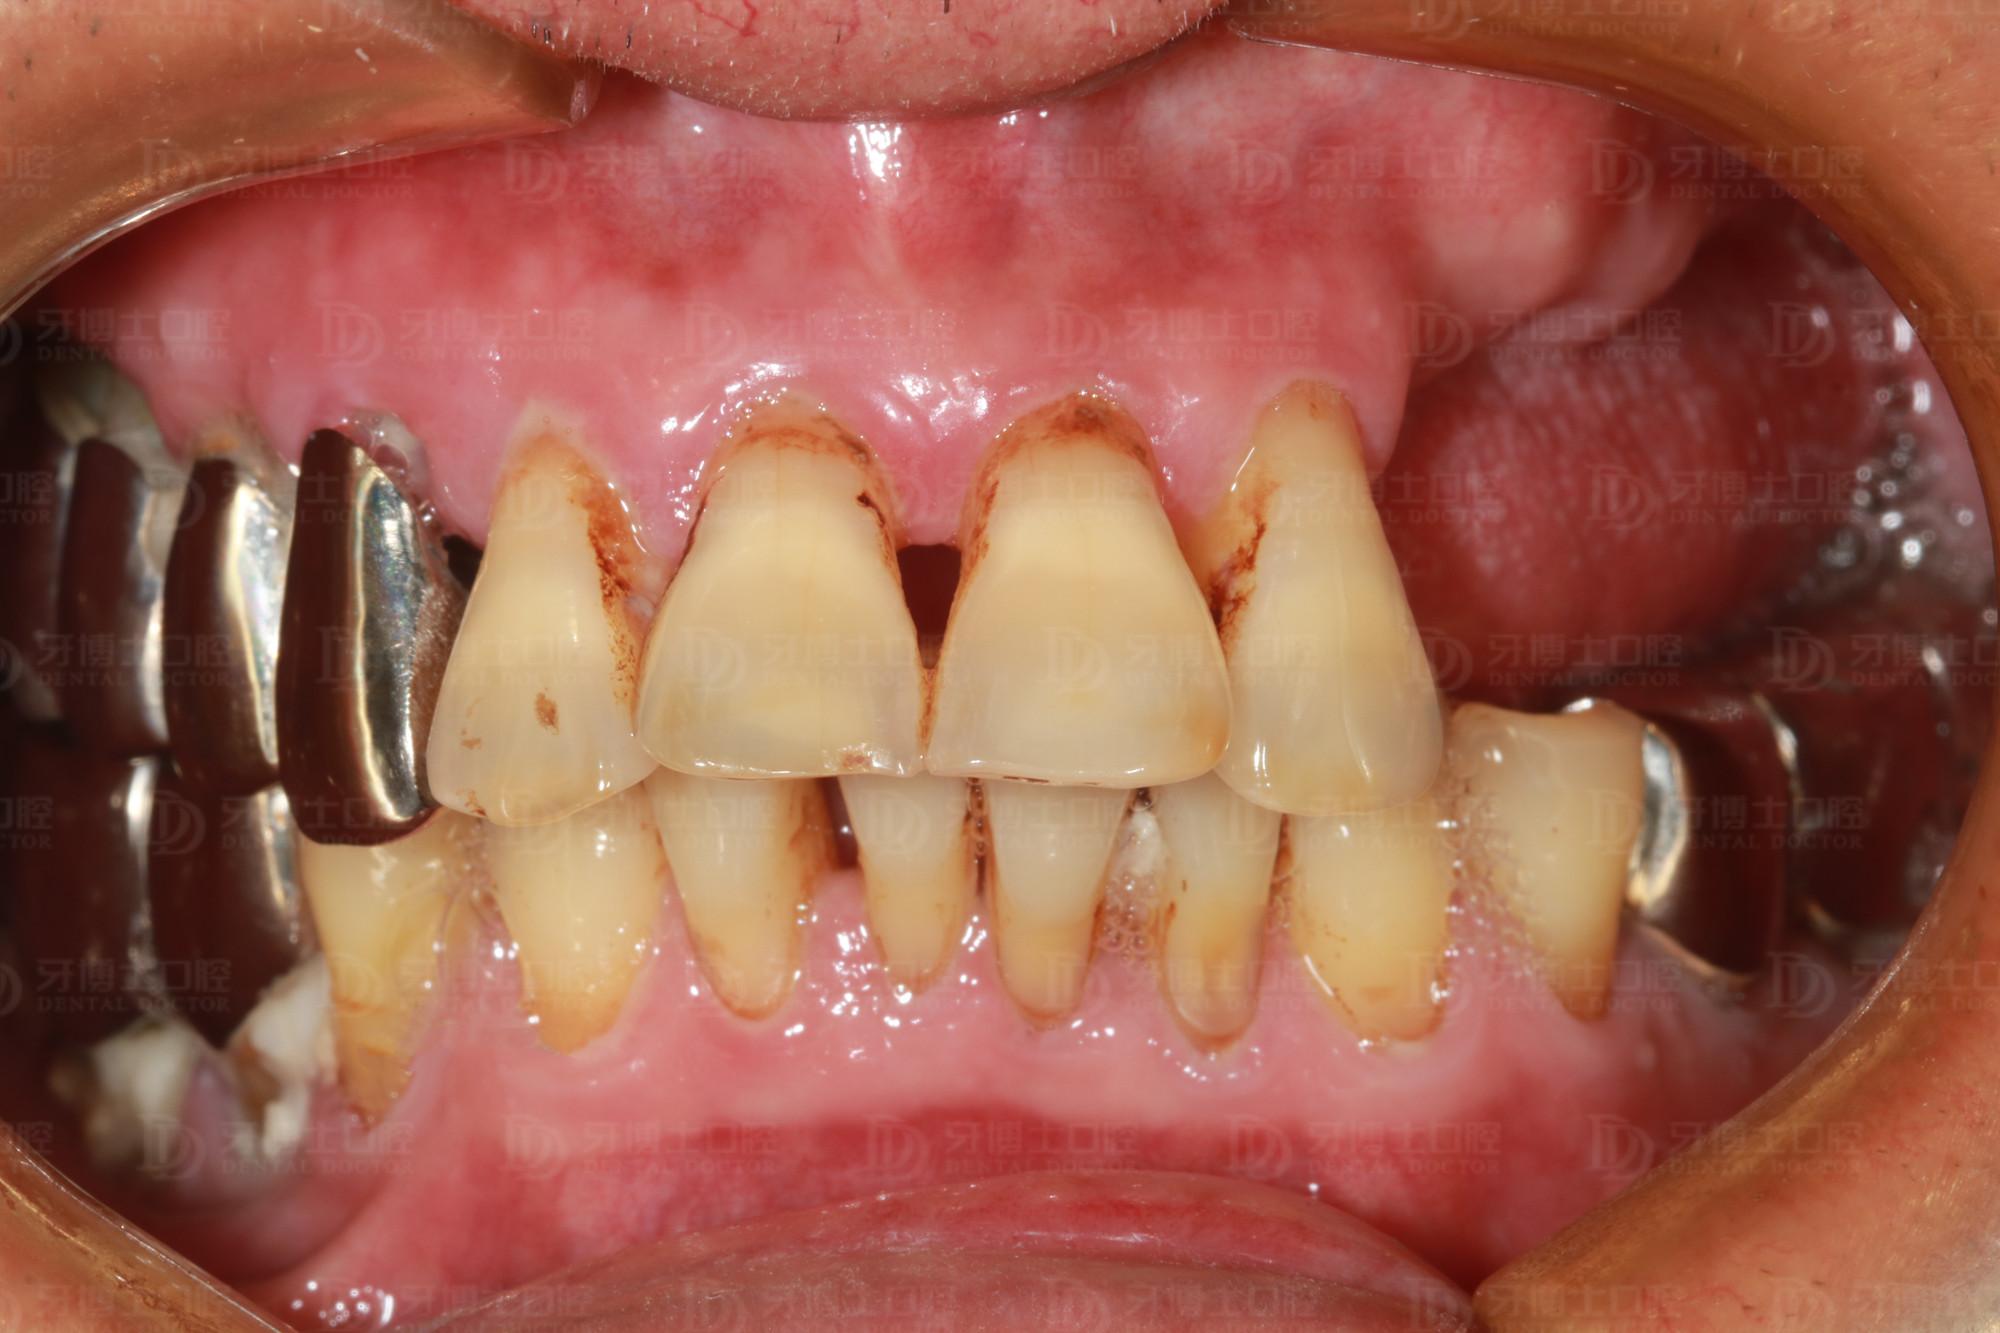

年近七旬的周老爺子(化名)牙齒缺失多年,上排牙只剩4顆前牙。前些年做的一側(cè)不銹鋼牙松得厲害,因為長期用那一側(cè)牙咀嚼,導致牙齒的牙根全部咬壞掉了,醫(yī)生開玩笑說“你這牙很脆弱了,打個噴嚏就會掉下來”。

據(jù)醫(yī)生介紹,像周老這種情況在臨床上很常見,后邊大牙缺失,咀嚼時前面三顆牙帶后面兩顆牙,咀嚼時間久了,形成杠桿作用,加上前面牙齒又負荷過重,牙根就全部斷掉了,只能拔除。

種牙前